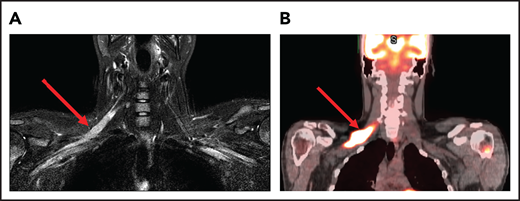

A 25-year-old man presented with fatigue with abdominal and bone pain, evaluation of which led to the diagnosis of a high-grade DLBCL with MYC and BCL2 rearrangements. Upon completion of treatment with 6 cycles of R-EPOCH (rituximab-etoposide, prednisone, vincristine, cyclophosphamide, and doxorubicin) and prophylactic intrathecal (IT) methotrexate, he developed severe pain in his right shoulder and left leg, associated with numbness of his left foot. Over the next month, his symptoms progressed, and he developed worsening pain and weakness in the right arm and bilateral foot drop. He was then diagnosed with Parsonage-Turner syndrome, an idiopathic brachial plexopathy, and treated with methylprednisolone, which did not help. Subsequently, an MRI of the brachial plexus showed increased enhancement and FDG-PET scan showed increased uptake in the right brachial plexus and bilateral sciatic nerves (Figure 1). Finally, he was diagnosed with neurolymphomatosis. He responded to treatment with HD-MTX and cytarabine and made a full recovery.

Brachial plexus MRI and FDG-PET scan of a patient with neurolymphomatosis. (A) An axial T1-weighted image after gadolinium contrast shows enhancement of the right brachial plexus. (B) FDG-PET scan shows an increase in FDG uptake in the right brachial plexus.